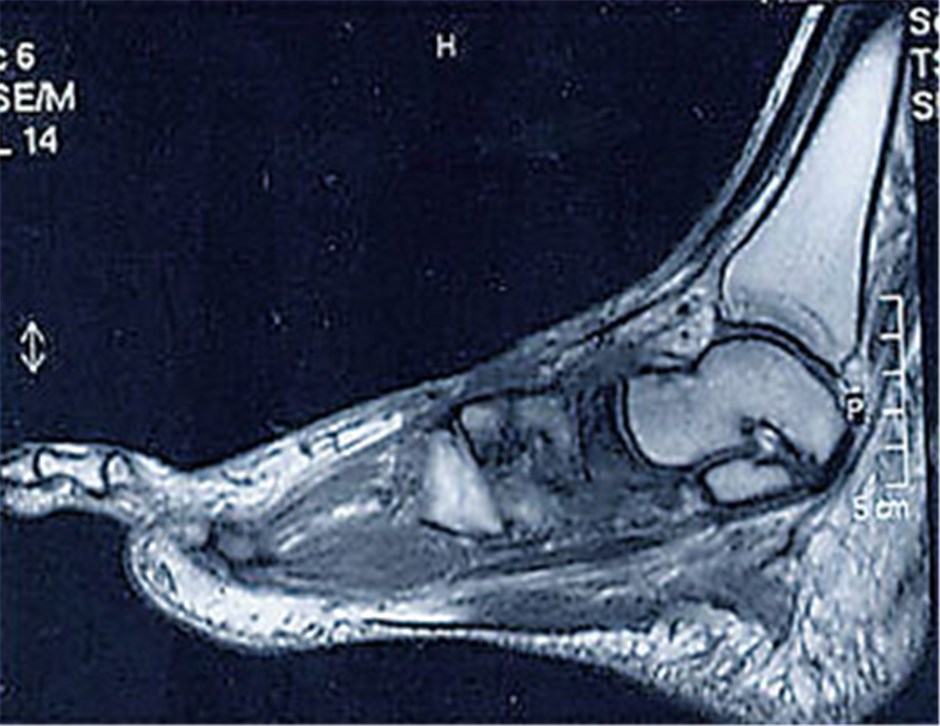

Wenn der Fuß schmerzlos zerstört wird